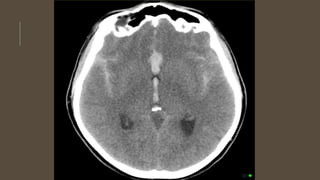

INVESTIGATIONS

• CT scan

• CT angiogram

• MRI and MRA

• DSA

INVESTIGATIONS • CT scan •CT angiogram • MRI and MRA • DSA